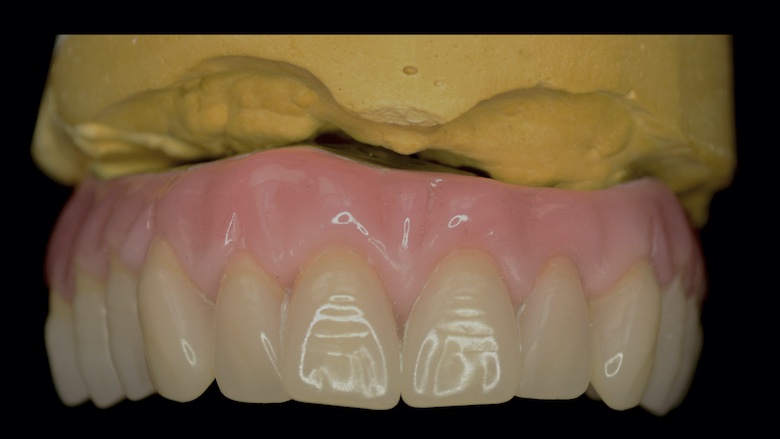

Restauración con implantes finalizada.

La implantología volvió a los pacientes más ambiciosos y demandantes de importantes rehabilitaciones, y con justa razón. Hoy en día, prácticamente no hay límites ni etarios ni resortivos-resectivos en los cuales no pueda lograrse la mayor de las rehabilitaciones, el mayor gold estándar, al que los pacientes pueden aspirar: me refiero, ni más ni menos, que a reconstituir su arco dentario completo fijo. Incluso con la posibilidad de remoción y mantenimiento que un simple mortal no implantado no tiene.